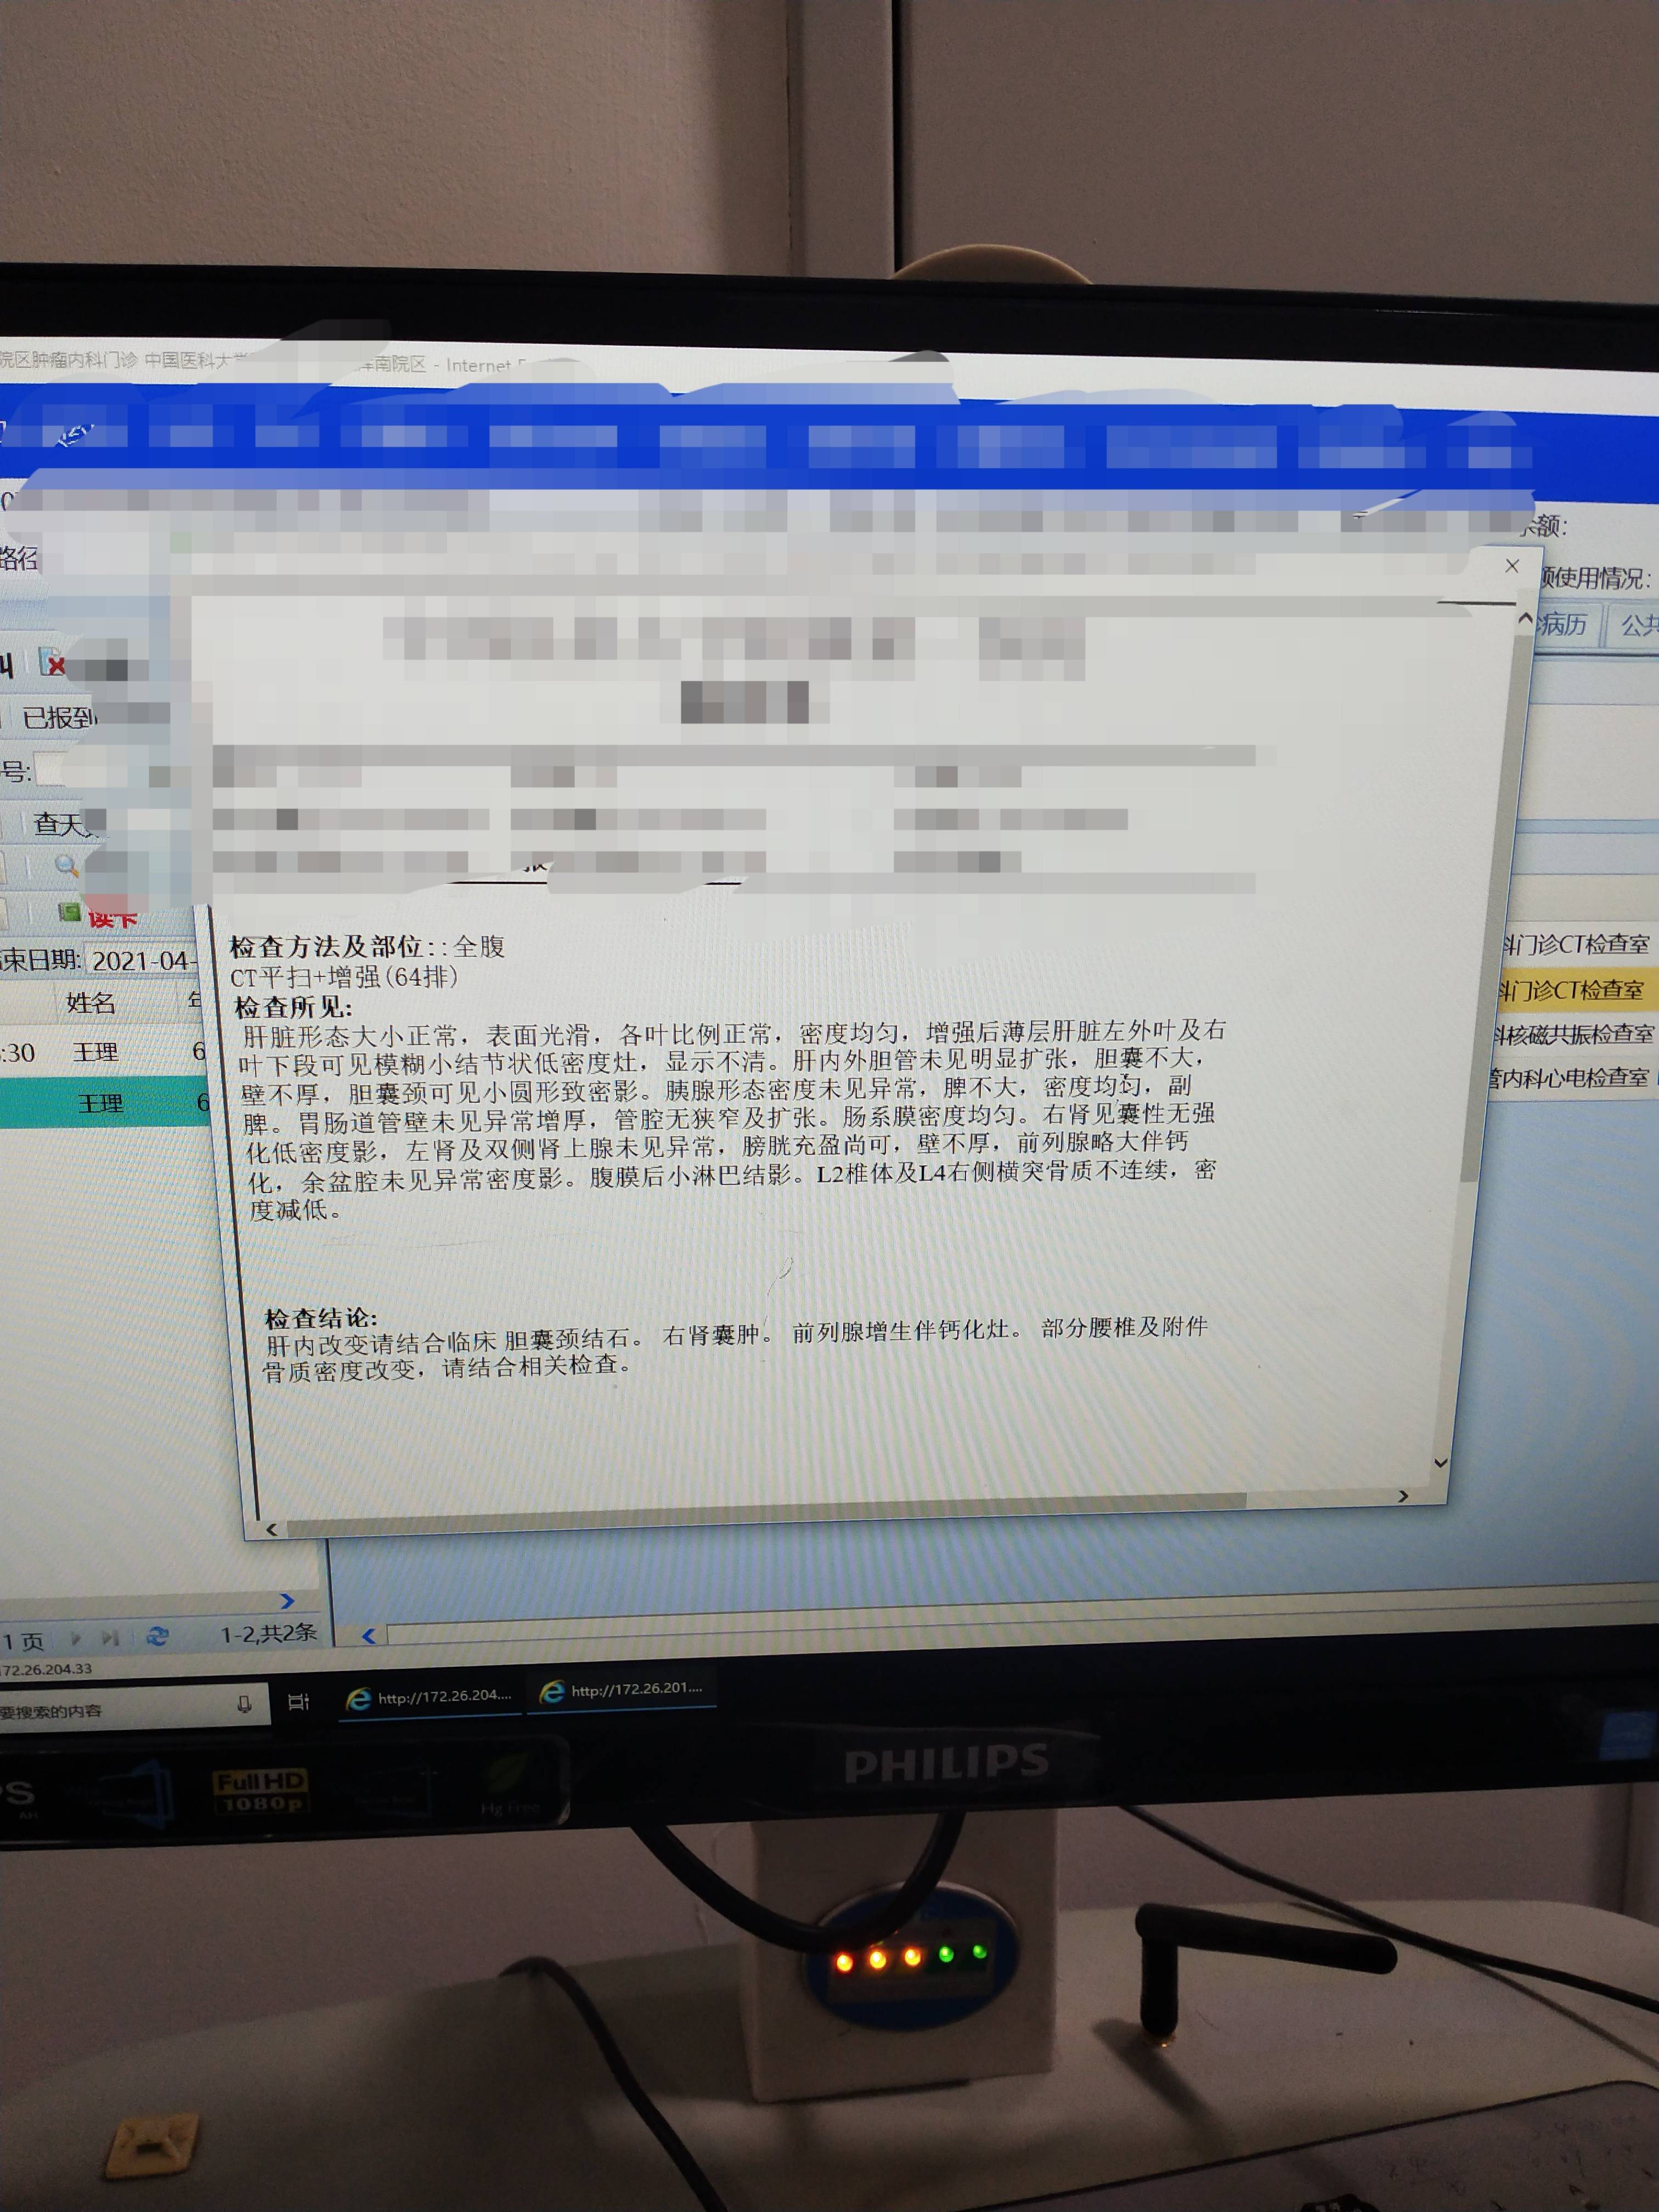

4化后全腹CT: